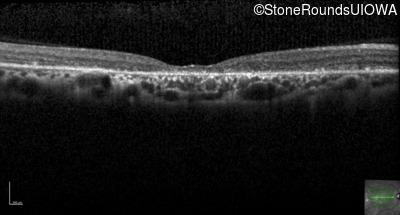

Optical Coherence Tomography - Right - 20/40

Exemplar / OCT Stack

OCT Stack